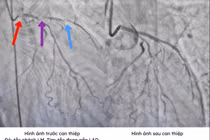

Sau khi có lại nhịp tim, bệnh nhân được chuyển ngay đến khoa Hồi sức tích cực - Chống độc (HSTC - PCĐ). Tại đây, bác sĩ cho thực hiện các xét nghiệm cần thiết, xác định nguyên nhân cốt lõi gây ngừng tim là tình trạng rối loạn điện giải, hạ kali máu nặng.

Để bảo vệ sự sống và hạn chế di chứng não cho người bệnh, ê–kíp hồi sức đã triển khai Hạ thân nhiệt để bảo vệ tế bào não, lọc máu liên tục điều chỉnh toan kiềm, điện giải.

Qua các kết quả xét nghiệm và chụp chiếu bác sĩ phát hiện nguyên nhân gốc rễ khiến chị X bị hạ kali máu dẫn đến ngừng tim là do u tuyến thượng thận. Đây là một bệnh lý hiếm gặp, làm thay đổi các hormone trong cơ thể, gây tổn hại nghiêm trọng đến các cơ quan và nguy hiểm đến sức khỏe nếu không được phát hiện sớm.